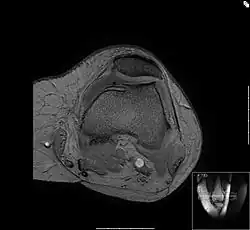

Die Bewegungsprüfung zeigt bei der Chondropathia patellae Reibegeräusche oder ein Knirschen im Gleitlager der Kniescheibe sowie häufig einen Kniescheibenanpressdruck. Der Arzt kann bei der körperlichen Untersuchung bestimmte Phänomene auslösen, die allesamt den Reizzustand des Kniescheibengleitlagers nachweisen. Reizergüsse oder Kapselschwellungen können auftreten, sind aber nicht unbedingt vorhanden. Es gibt eine spezielle Lagerung des Kniegelenkes beim Röntgen, in der das Gleitlager zwischen Kniescheibe und Oberschenkelknochen in verschiedenen Funktionszuständen dargestellt wird, die Aussagekraft ist jedoch begrenzt in Bezug auf die Knorpelschädigung. Gut beurteilt werden kann hingegen die Form des Gleitlagers, also die korrespondierenden Gelenkanteile des Femoropatellargelenkes. Eine ungünstige Kniescheibenform beispielsweise, die sogenannte Patelladysplasie führt zu einer nachteiligen Druckverteilung auf den Knorpel der Kniescheibenrückfläche und stellt somit eine Prädisposition für die Entstehung der Chondropathia patellae dar. Das MRT als weiteres bildgebendes Verfahren zeigt im Gegensatz zur Röntgendiagnostik auch krankhafte Veränderungen des Knorpels selbst.

Das Bild zeigt einen Querschnitt durch die Knochen des Oberschenkels, die Femurkondylen. Im oberen Bereich des Bildes liegt die Kniescheibe. Gut zur Darstellung kommt die Feinstruktur des Knochens, die sogenannte Spongiosa.

Zwischen Kniescheibe und dem Oberschenkel ist die Knorpelschicht zu sehen, der feine, graue Saum dazwischen ist die Gelenkflüssigkeit. Im unteren Teil des Bildes ist die Kniekehle mit den durchlaufenden Gefäßen. Die Gelenkkapsel umgibt den Oberschenkel und die Kniescheibe, man sieht angedeutet die Faserstruktur. Das wabige, hell dargestellte Material ist Körperfett.